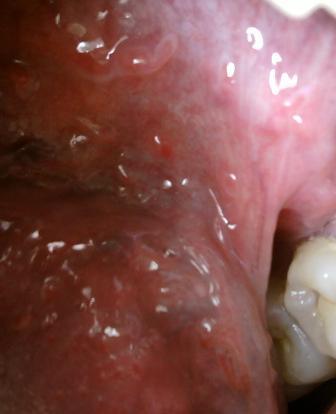

石家庄九州皮肤病医院 > 尖锐湿疣 > > > 哪家医院可以彻底根治尖锐湿疣对于尖锐湿疣疾病的治疗,希望大家应该引起重视,切记不可以耽误诊治,否则病情加重之后治疗难度会大大增加。早日远离病魔是被疾病困扰的患者的最大心愿。

哪家医院可以彻底根治尖锐湿疣资深专家表示:患者朋友们应该对于疾病有一个正确的任何和了解,尖锐湿疣并不是不治之症,但是只要广大患者朋友们及时就诊,经过专业的治疗,疾病是可以治愈的。尖锐湿疣对人体的危害有哪些尖锐湿疣如果不及时进行治疗,就会容易诱发一些炎症,导致不孕不育,更严重者还会诱发癌症,尖锐湿疣是比较顽固的,所以建议大家应该坚持治疗。中医疗法,其采用辨证施治,结合内外因对症下药的特点,因此病情比较长,需要长期的进行治疗。